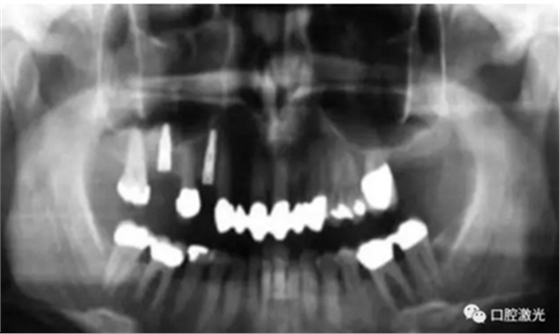

#33,#43显示存在种植体周围炎

气化切除种植体周围的软组织可以获得一个干净的种植体表面以及去除感染的生物组织层。其目的是稳定种植体周围的组织结构,从而避免骨的缺失导致种植体的失败。但由于种植体的数量逐步增加以及患者年龄的逐渐增大,出现种植体周围炎的概率会显著提高。口腔激光疗法的出现,扩大了种植体周围炎的治疗范围并提供了维持健康的种植体的一种全新方法。